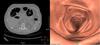

HD?

Diverticulite.

Diverticulite aguda à esquerda com aumento acentuado da ecogenicidade da gordura ao redor de um divertículo.